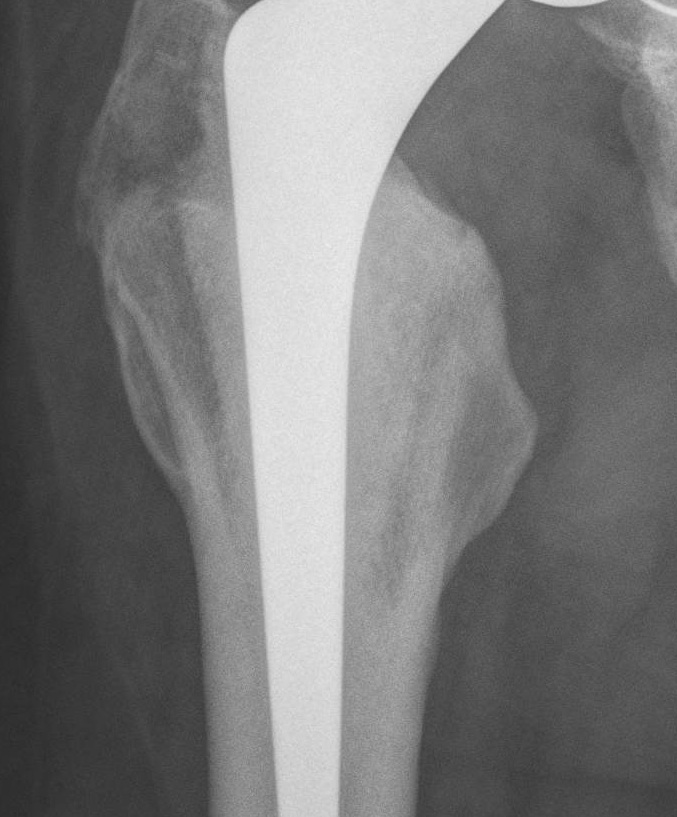

Barrack's femoral component cementation quality grading system

| Grade | Definition |

|---|---|

| A | Complete filling of the medullary canal, without radiolucent lines between the cement and the bone (white-out) |

| B | Radiolucent line covering up to 50% of the cement-bone interface |

| C | Radiolucent line covering between 50% and 99% of the cement-bone interface or incomplete cement mantle |

| D | Complete radiolucent line (100%) at the cement-bone interface and/or absence of cement distally to the end of the stem |

Grade A Grade B Grade C Grade D